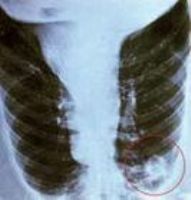

肺炎衣原体肺炎的肺部X线检查常显示肺亚段少量片状浸润灶,广泛实变仅见于病情严重者中。大部分患者血白细胞在正常范围。

本症临床表现无特异性,与支原体肺炎楥相似。起病缓,病程长,一般症状轻,常伴咽、喉炎及鼻窦炎为其特点。上呼吸道感染症状消退后,出现干湿啰音等支气管炎、肺炎表现。咳嗽症状可持续3周以上。白细胞计数正常,胸片无特异性,多为单侧下叶浸润,表现为节段性肺炎,严重者呈广泛双侧肺炎。病原学检查与沙眼衣原体肺炎一样,从气管或鼻咽吸取物做细胞培养,肺炎衣原体阳性。或用荧光结合的肺炎衣原体特异性单克隆抗体来鉴定细胞培养中的肺炎衣原体。PCR检测肺炎衣原体DNA较培养更敏感,但用咽拭子标本检测似不够理想,不如血清学检测肺炎衣原体特异性抗体。微量免疫荧光(MIF)试验检测肺炎衣原体仍最敏感。特异性IgM抗体≥1:16或IgM抗体≥1:512或抗体滴度4倍以上增高,有诊断价值。

白细胞计数正常,胸片无特异性,多为单侧下叶浸润表现为节段性肺炎,严重者呈广泛双侧肺炎。病原学检查与沙眼衣原体肺炎一样从气管或鼻咽吸取物做细胞培养,肺炎衣原体阳性。或用荧光结合的肺炎衣原体特异性单克隆抗体来鉴定细胞培养中的肺炎衣原体PCR检测肺炎衣原体DNA较培养更敏感,但用咽拭子标本检测似不够理想,不如血清学检测肺炎衣原体特异性抗体微量免疫荧光(MIF)试验检测肺炎衣原体仍最敏感。特异性IgM抗体≥1:16或IgM抗体≥1:512或抗体滴度4倍以上增高,有诊断价值。